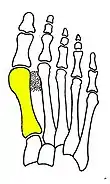

Syndesmosis procedure addresses specifically the two fundamental problems of metatarsus primus varus deformity that gives rise to the bunion deformity. They are leaning and instability of the first metatarsal bone . Syndesmosis procedure uprights the leaning first metatarsal bone with strong binding sutures between it and the second metatarsal bone (Fig. 2) and then also stabilizes it uniquely by creating a fibrous connecting bridge between these two bones (Fig. 3, 4). First metatarsal bone can be readily realigned because by definition of the metatarsus primus varus deformity its first metatarsal is abnormally loose and mobile.

The surgical technique of syndesmosis procedure originated from the osteodesis procedure that was first described by Botteri in 1961.[6] It has since been studied and reported by Pagella in 1971,[7] Irwin in 1999[8] and Wu in 2007.[2] Syndesmosis itself is a normal anatomical structure for the purpose of connecting two parallel long bones side by side, such as the tibia and fibula bones. The naming of syndesmosis procedure was thus to reflect the essence of the technique which is to create a “syndesmosis” mechanism to provide permanent stability to the first metatarsal to prevent recurrence. Both the bone-binding-sutures and syndesmosis-connection concepts are unique and revolutionary in a world of bunion surgery overwhelmingly dominated by osteotomy (bone-breaking) tradition.